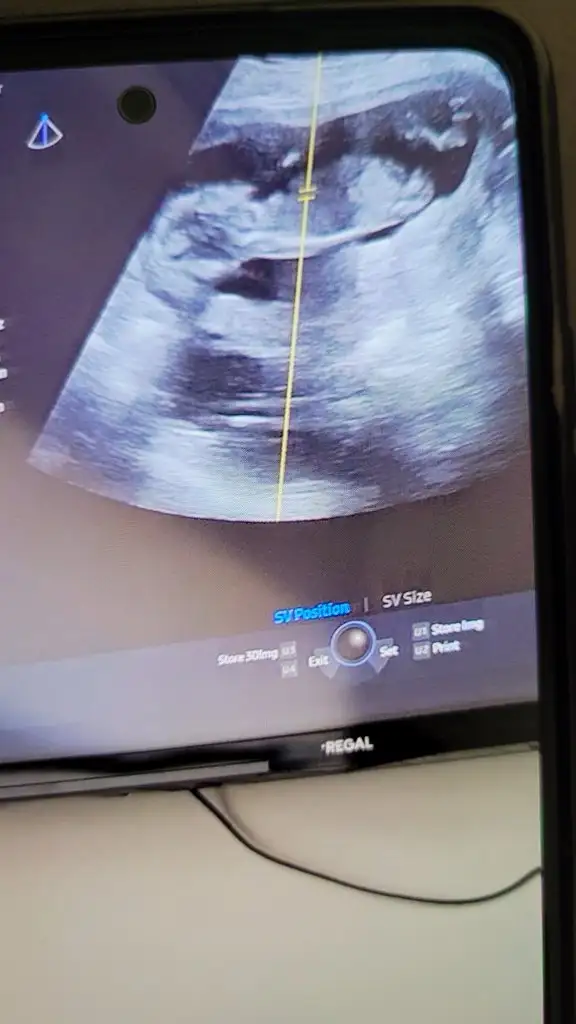

bana da yorum yapın lütfen 12+4

N Nakafile merhaba. Benim 12. haftada sırtı dönük mu anlayamadigim bir ultrason kağıdım var bu haftayı hevesle bekledim cocugum çok belirsiz bakayım siz cinsiyeti hakkinda ne diyeceksiniz acaba rica etsem yorumlar misniz :')